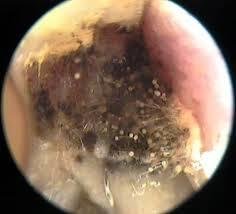

otomycosis

fungal infection

itching, burning, pain, discharge, hearing loss

Skin conditions and humid environment

Treatment: prescribed ear dropsa